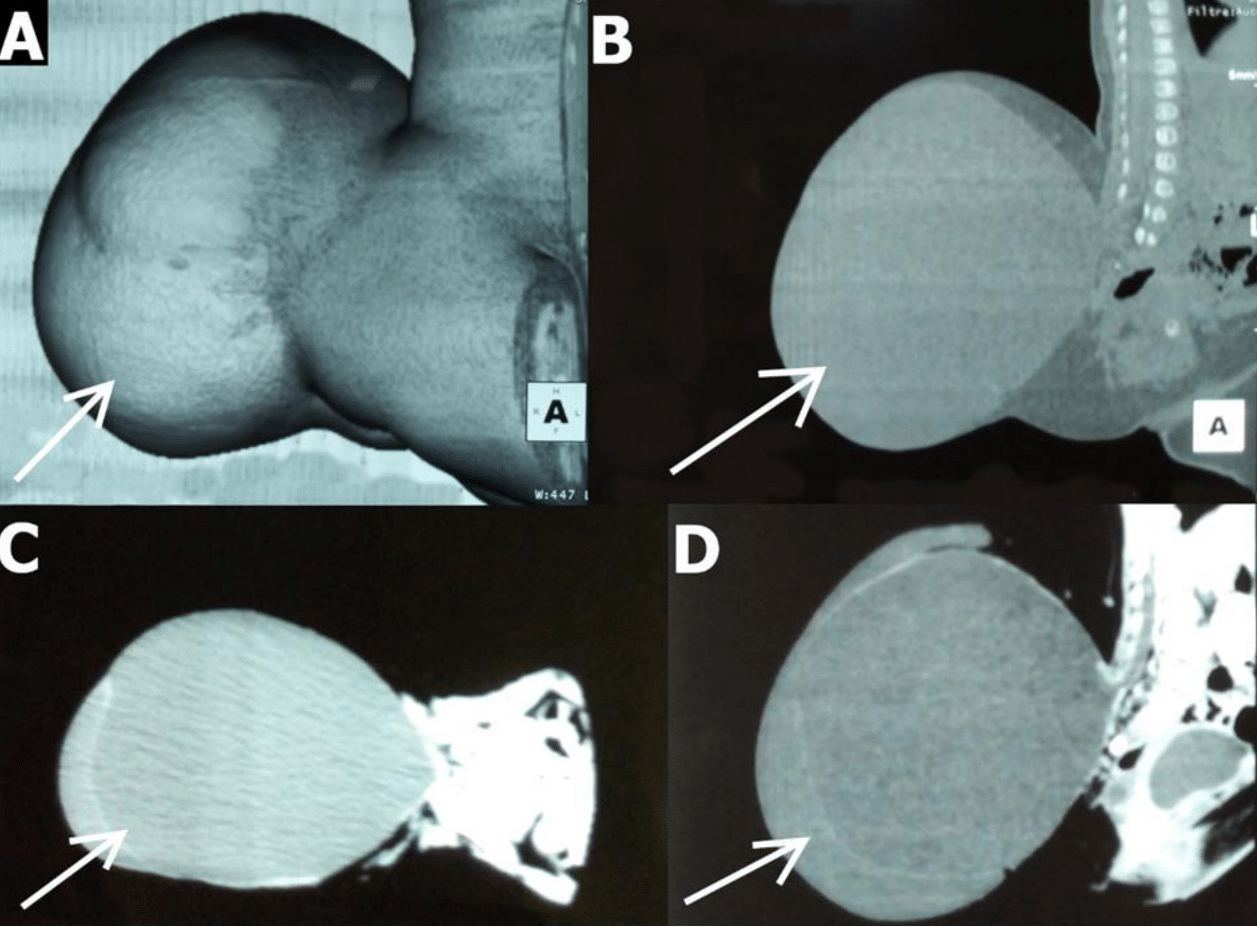

4-month-old male infant, born at term by caesarean section at 3.6 kg, eutrophic with a large lumbosacral mass, second child of consanguineous parents. He was the second child of consanguineous parents, the result of a poorly monitored mono-fetal pregnancy with no notable antecedents. He was referred to us by a peripheral center for management of spina bifida. On admission, he was conscious with normal general condition, normal symmetrical pupils and no neurological deficit. The swelling had been progressively increasing in size since birth and currently measured 17 cm x 15.5 cm x 10 cm; it was globular, cystic, fluctuating, painless, and threatened to rupture at any time; the skin covering the mass was normal and shiny (Figure 1). The baby's respiratory, digestive and cardiovascular examinations were unremarkable. The preoperative CT scan of the spine showed a posterior arch anomaly at the level of vertebrae L4 to S1, as well as a voluminous herniation of the cerebrospinal fluid-filled meninges (Figure 2). The diagnosis was lumbosacral meningocele with imminent unruptured rupture. Preoperative haemotological and biochemical findings were within normal limits. Surgical excision and repair were indicated, he was prepared for surgical cure and taken to the operating room. In the operating room, after general anesthesia, an orange-peel incision was made. During surgical cure, the residual neural plate was exposed and placed in the sheath (Figure 3). The post-operative course was complicated by an infection of the surgical site, but thanks to appropriate management the evolution was favorable.

Figure 1 Operating room images of case 1, showing: A,B,C,D) giant lumbosacral meningocele presenting as a large, globular, cystic, fluctuating, translucent mass (white arrows).

Figure 2 Preoperative CT images of case 1, showing : A,B,C,D) a posterior arch anomaly at the level of vertebrae L4 to S1, and a large herniated meninges filled with cerebrospinal fluid (white arrows).